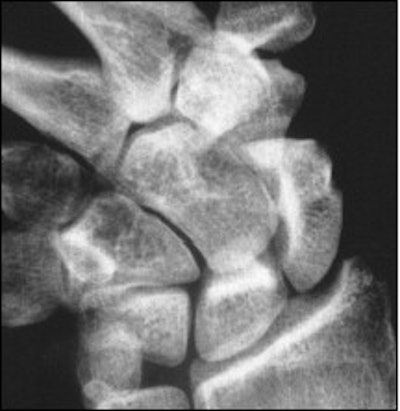

![]() ![]() |

| Forty-nine-year old woman with acute trauma of the wrist. Conventional radiography and panoramic radiography were performed two weeks after injury. Conventional radiographs (above) show no evidence of fracture. |